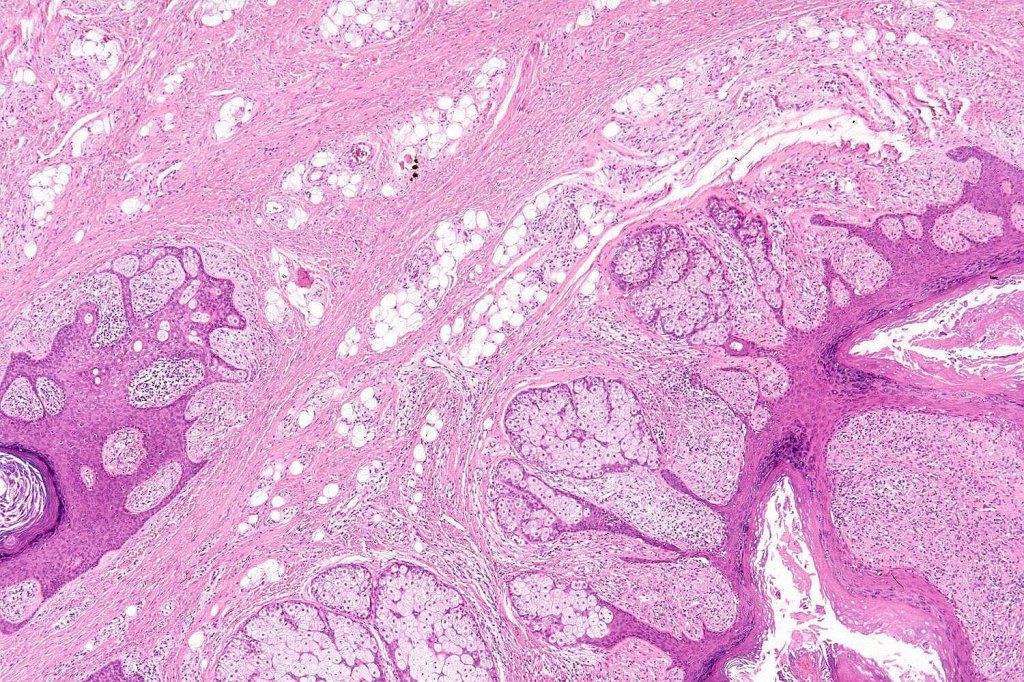

•Circumscribed dermal nodule with a characteristic silhouette

•An infundibular cyst is surrounded by laminated dermal collagen, elastic fibers, blood vessels, adipocytes & spindle cells separated from the adjacent dermis by a retraction artifact

•The cyst contains keratinous debris, and its wall shows conspicuous sebaceous & sometimes hair follicular elements are also evident